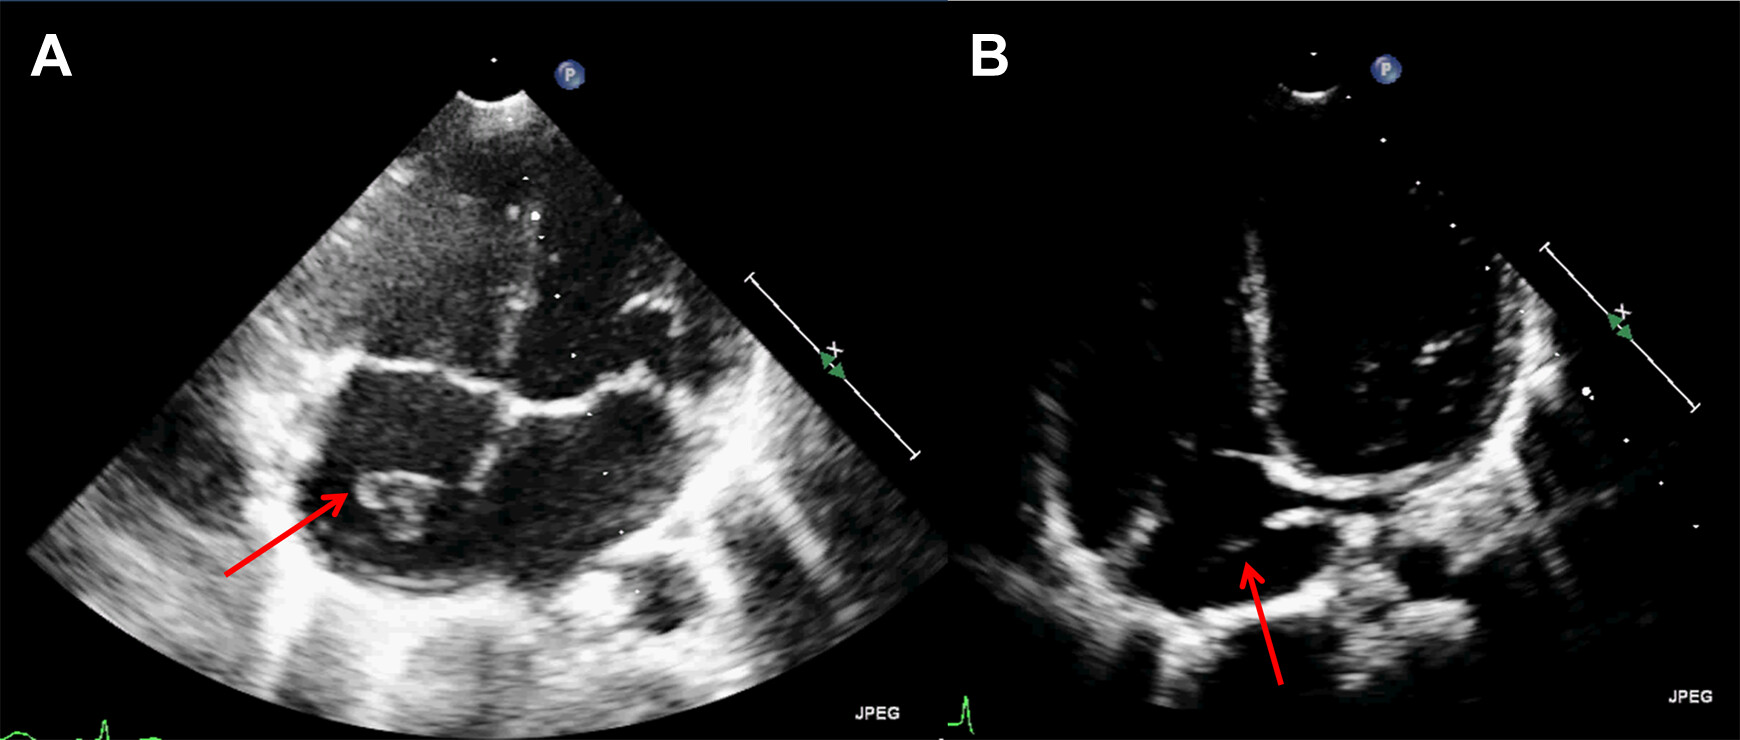

Hi team! Since we perform NP-POCUS in resuscitating septic patient we might have or might encounter this image/assessment in our apical four chamber view of the heart. The Chiari network, encountered infrequently in the right atrium, is a fenestrated, net-like embryonic remnants of valves of sinus venosus, lying closely in relation to the inferior vena cava and coronary sinus, sometimes connecting these with other right atrial structures…

sometimes it poses diagnostic difficulties during echocardiography where it could be misdiagnosed as right atrial thrombi, tumors and vegetations…- NCBI

image credit to Sage Journals